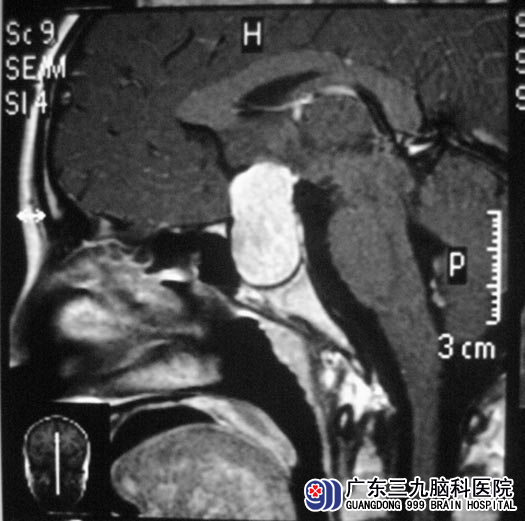

一年前,小刘开始出现闭经,当时没有治疗。去年年底出现泌乳,头颅MR检查提示鞍区占位,考虑垂体腺瘤,泌乳素检查提示泌乳素增高,口服溴隐亭治疗。父母计划高考后再做手术。但是高考前她总是频频头痛,已经严重影响到她的学习,父母和小刘商量后决定放弃高考,立即手术治疗。http://www.999brain.com/

广东三九脑科医院垂体瘤诊疗中心 鲁明主任初步检查:视力、视野正常,查阅头颅MR见肿瘤向下生长,决定经鼻入路微创手术治疗。由鲁明主任主刀,在神经导航仪定位下行经鼻蝶垂体瘤切除术,术中见肿瘤呈灰白色,质软,易剔除,镜下行肿瘤切除术。术后小刘未出现脑脊液鼻漏等常见术后并发症,泌乳素水平基本恢复正常。术后病理结果为:垂体腺瘤。

▲手术前